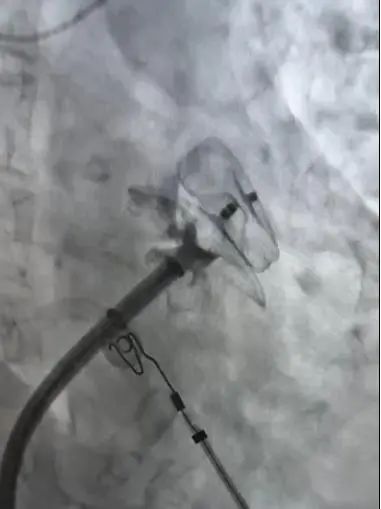

微信圖片_20250414082733

術(shù)中進(jìn)行房顫環(huán)肺靜脈隔離